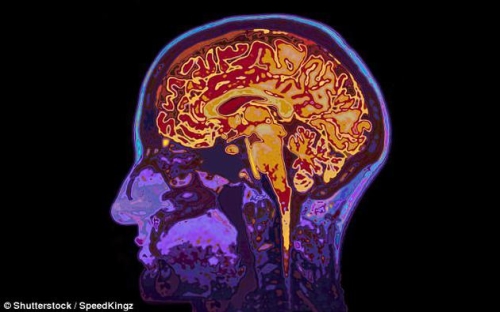

在一项新研究中,两位生物伦理学家表示,连接大脑的“交感神经科技”(neurotechnology)有可能发展到非常先进的程度,并且大规模应用,从而很容易成为黑客的目标。入侵者可能会不经授权地进入大脑,监控甚至删除用户的思想。

研究人员在论文中阐述了这一令人震惊的预测,指出交感神经科技的发展或许有一天会破坏我们的思想隐私权。因此,他们提出应该制定新的人权法律,以应对大脑科技的飞速发展,保护人们的“思想自由”不被剥夺。

交感神经科技的发展,包括先进的大脑成像技术和人机界面的发展,已经使这些技术从临床应用转移到消费领域。尽管这些技术可能给个人和社会带来好处,但也存在技术被滥用或误用的风险。研究者表示,如果出现这种情况,将对人类的个人自由带来前所未有的威胁。